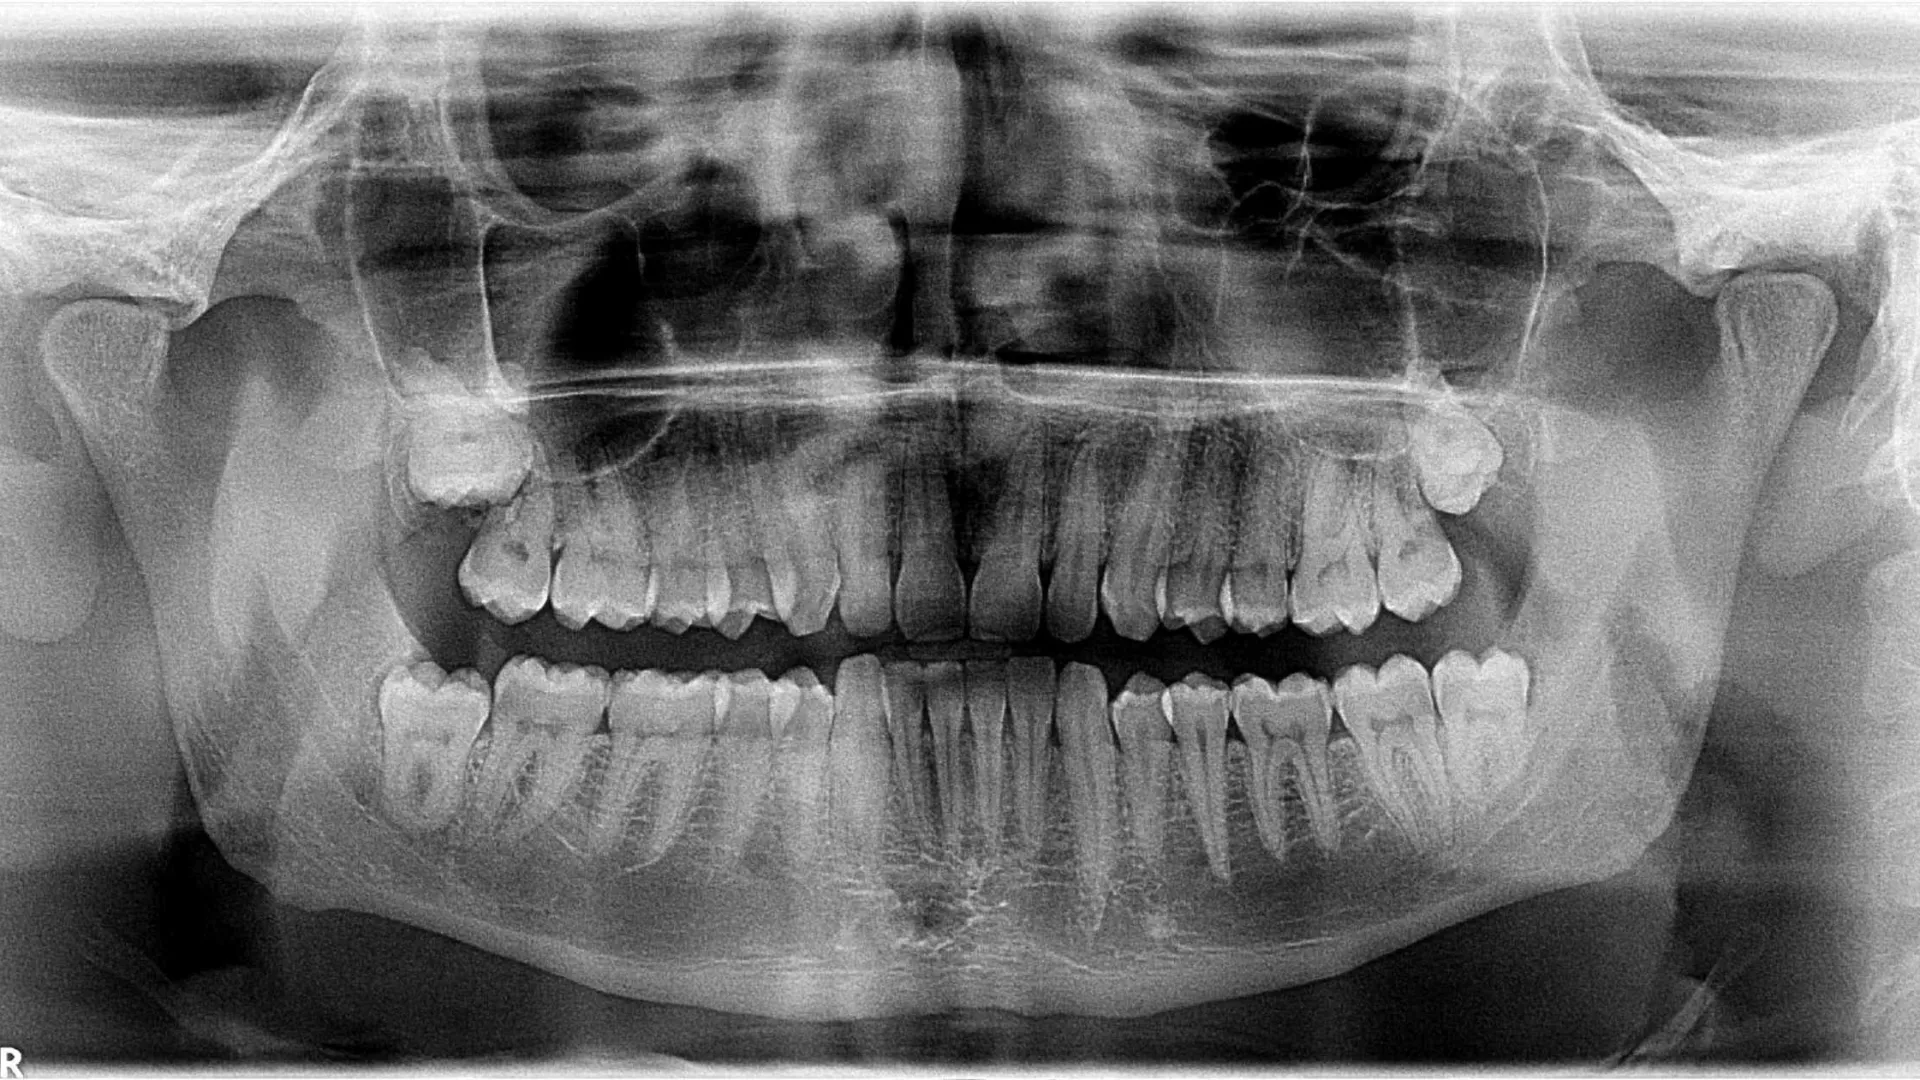

Os atos cirúrgicos mais comuns são as extrações dentárias. As extrações dentárias têm diversas indicações, como cáries extensas, dentes fraturados, dentes inclusos (sisos).

• Enucleação de quistos dos ossos maxilares;

• Exposição de dentes inclusos para tração ortodôntica;

• Quistos, tumores e outras lesões ósseas dos maxilares;